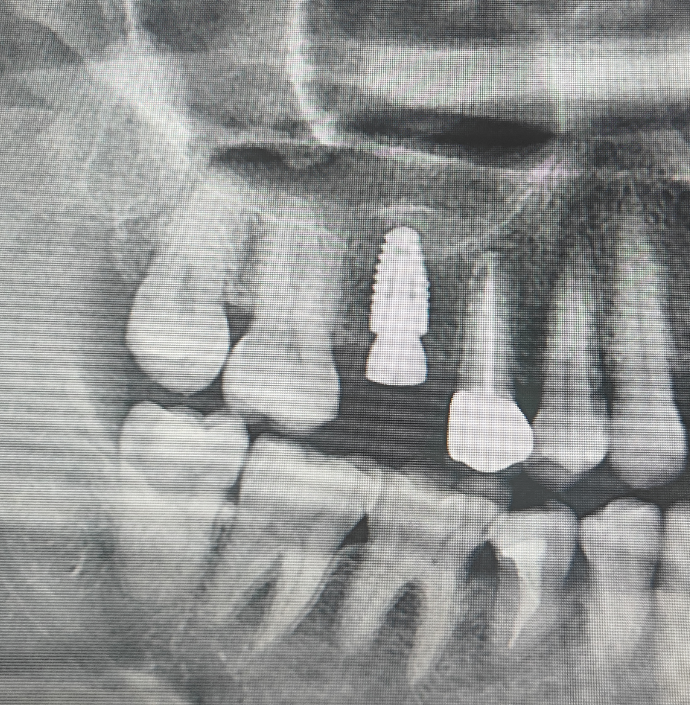

最近的病例给大家看一下。